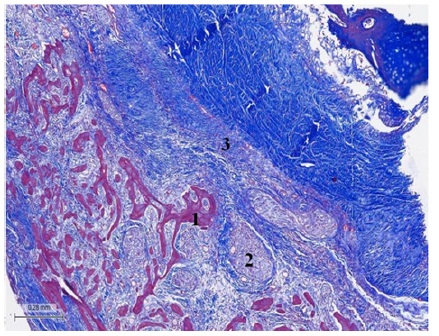

Figure 3: (Bovine heart). Masson’s trichrome technique. 25x. Tangential section of the fulcrum. Fulcrum osseous trabeculae including plexuses with neurofilaments. 1. Osseous tissue. 2. Terminal plexuses. 3. Fibroconnective tissue.

Figure 4: 36-day newborn human heart. Magnification 20x. The fulcrum with cartilaginous matrix is seen with the myocardium and the adjacent Atrioventricular Node (AV).